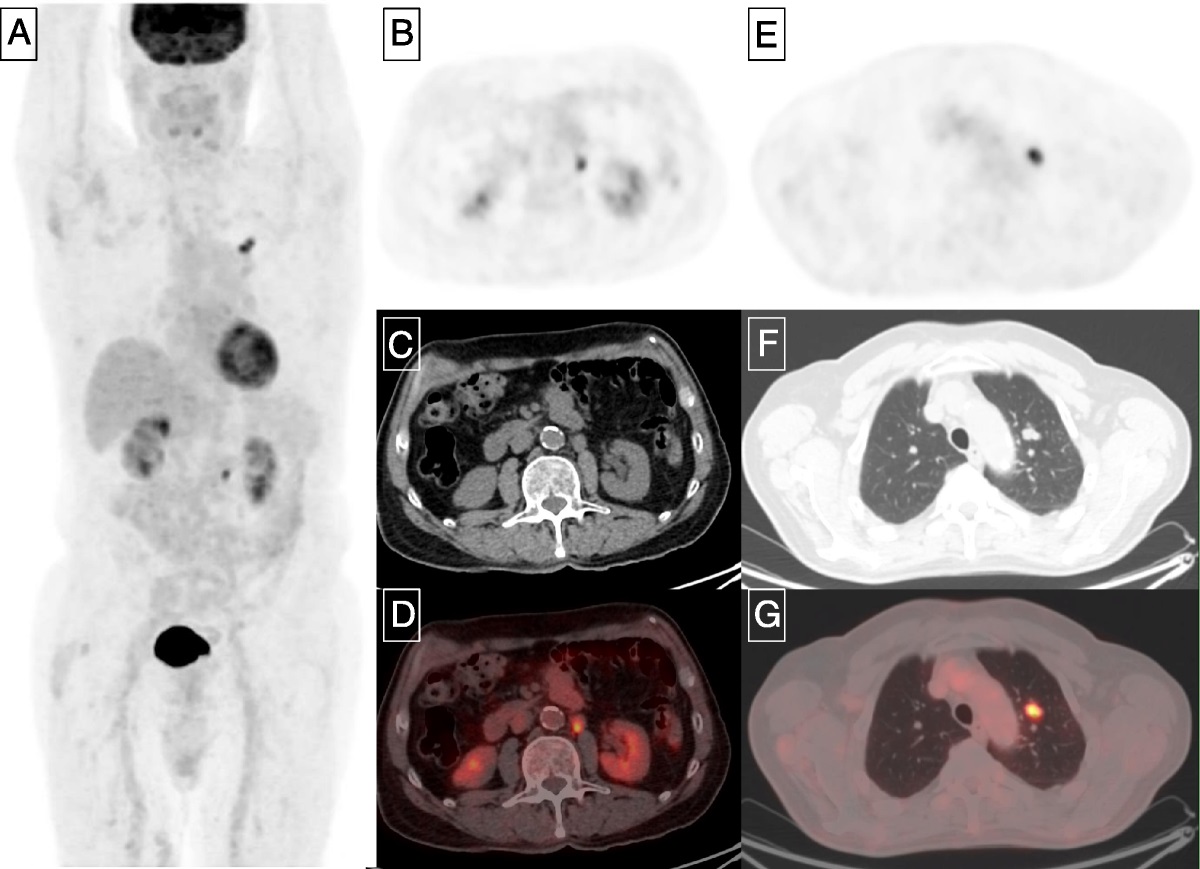

PET evaluation of changes in c-MET expression in metastatic #RenalCellCarcinoma under therapy with cabozantinib. Presentation by LenaUnterrainer UCLA. #SNMMI23 written coverage by Rashid K. Sayyid University of Toronto > bit.ly/3r5jsSh SNMMI